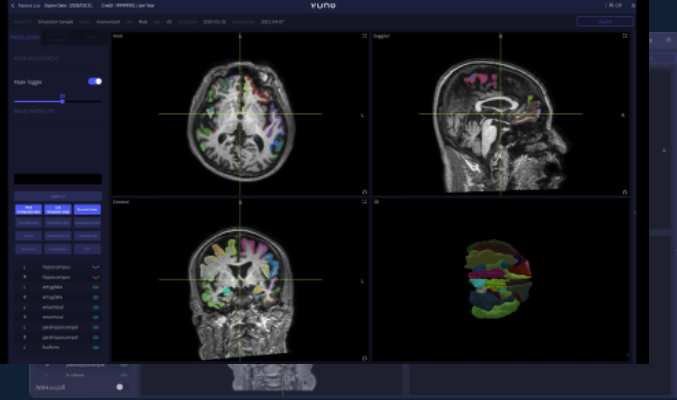

VUNO MED-DeepBrain

뇌 MRI 영상을 통해 위축 정도를 정량화 할 수 있으며 이를 통해 다양한 퇴행성 뇌질환 진단을 보조하는 소프트웨어.

뇌를 100개의 영역으로 분할하고 각 영역의 부피를 정상군과 대조하는 방법으로 위축도를 분석합니다.